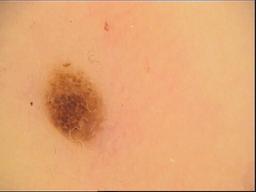

Skin lesion datasets provide essential information for understanding various skin conditions and developing effective diagnostic tools. They aid the artificial intelligence-based early detection of skin cancer, facilitate treatment planning, and contribute to medical education and research. Published large datasets have partially coverage the subclassifications of the skin lesions. This limitation highlights the need for more expansive and varied datasets to reduce false predictions and help improve the failure analysis for skin lesions. This study presents a diverse dataset comprising 12,345 dermatoscopic images with 40 subclasses of skin lesions, collected in Turkiye, which comprises different skin types in the transition zone between Europe and Asia. Each subgroup contains high-resolution images and expert annotations, providing a strong and reliable basis for future research. The detailed analysis of each subgroup provided in this study facilitates targeted research endeavors and enhances the depth of understanding regarding the skin lesions. This dataset distinguishes itself through a diverse structure with its 5 super classes, 15 main classes, 40 subclasses and 12,345 high-resolution dermatoscopic images.